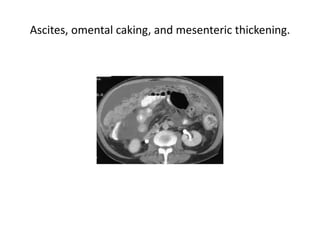

Ascites, omental caking, and mesenteric thickening.

Ascites, omental caking,and mesenteric thickening.